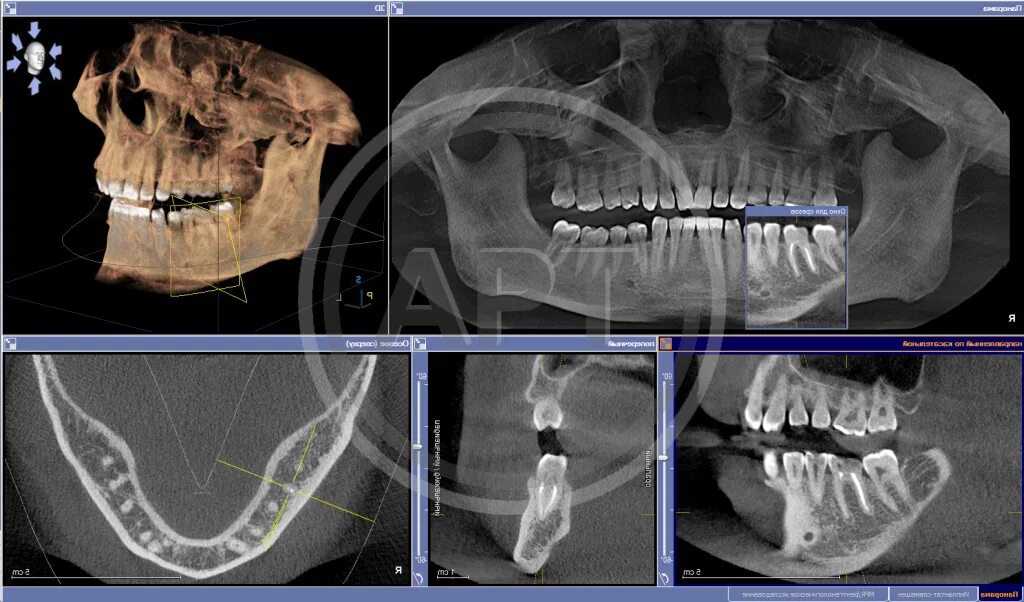

Кл кт